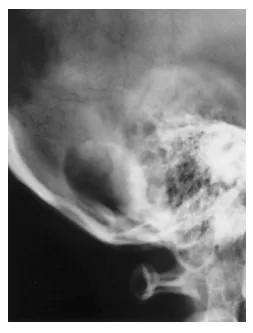

头颅X线片显示枕骨存在一溶骨性病变(图1)。

图1头颅侧位X线片显示枕下区一溶骨性病变。